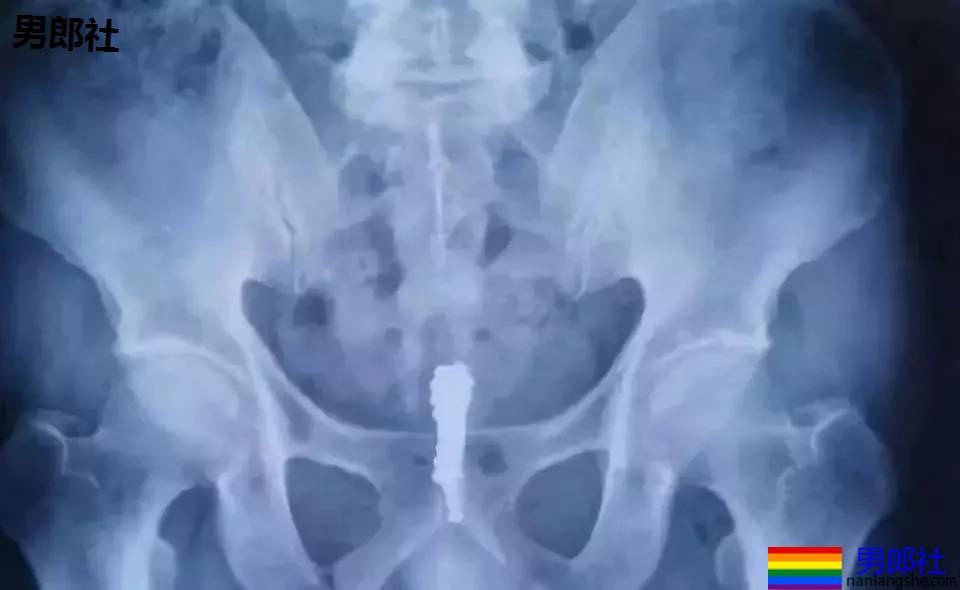

在拍了X光片以后,医生都有些吃惊,金属球可不止一颗,而是一串。金属球已通过尿道已经进入到了膀胱里。

医生介绍说,这是巴克球,是一种圆形、光滑、具有磁性的金属球,直径在2毫米左右,很容易造成膀胱的穿孔、感染。

以往,这类异物要想取出来,需在患者肚皮上做开刀手术。但这样的创伤较大,患者很痛苦。这次,医生采取了经尿道微创手术,只用了十几分钟,便将进入男子体内、各种颜色的磁力球成功取出。数一数,居然有28颗。